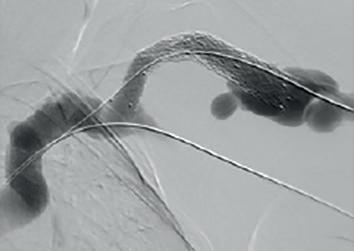

Example procedural outcome: treatment of Bond’s patient with a left brachiocephalic AVF that presented with a stenosis at the cephalic arch with aneurysmal segment.

(A) Fistulogram taken preintervention and (B) after deployment of WRAPSODY to treat. (C) Fluoroscopy of treated segment at 18 months (D) and patient’s arm at time of presentation

goals, and her pain was resolved overnight. She is due for her three-year angiogram this month— she has not had any issues with dialysis.”

Jones echoes Bond’s suggestion that Wrapsody is straightforward to use. “It tracks very well through the vessel, over the wire and through the stenosis. On deployment the device remains stable, and the trigger delivery system is very responsive.”

On the device’s design, Jones highlights its unique tri-layer configuration, with its polytetrafluoroethylene (PTFE) inner layer, its cell-impermeable layer, and expanded PTFE (ePTFE) outer layer that allows it to be embedded into the vessel wall. He also cites its optimised radial strength and relative compression resistance.

“For me,” he says, “one of the most interesting design features is the softened end-rows. These are designed in a scalloped fashion with the aim of reducing stress at the interface between the edge of the stent and the normal adjacent vessel, which will hopefully reduce the incidence of edge stenosis—the Achilles’ heel of stent grafts.”